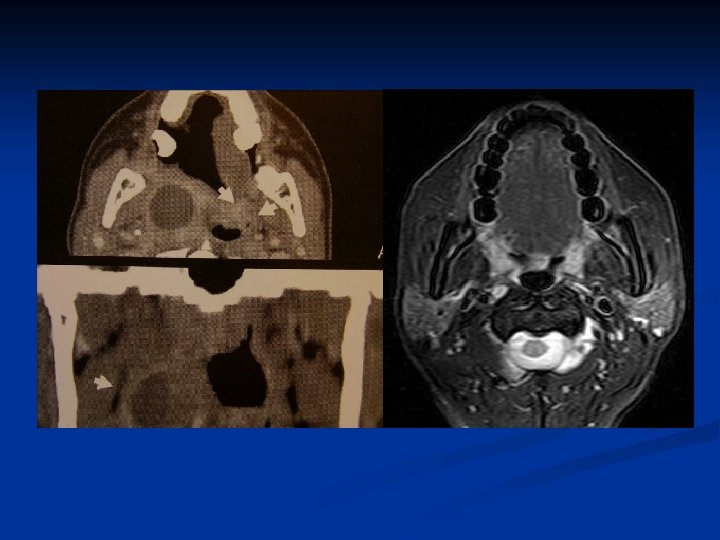

Nasopharynx n Keywords: -- Rosenmüller fossa, Torus tubarius , Eustachian tube orifice -- Pterygopalatine fossa (PPF) -- Parapharyngeal space (PPS) -- Retropharyngeal space (RPS) -- Prevertebral musculature -- Foramen lacerum-ICA (perivascular), -- Foramen ovale-V 3 (perineural)

Rosenmüller fossa, Torus tubarius , Eustachian tube orifice

940127 940930

Pterygopalatine fossa (PPF)

Parapharyngeal space (PPS) n n Fat Branches of cranial nerve V 3 Ascending pharyngeal artery Pharyngeal venous plexus

Retropharyngeal space (RPS) Fat n Lateral retropharyngeal nodes (of Rouviere) n Medial retropharyngeal nodes n